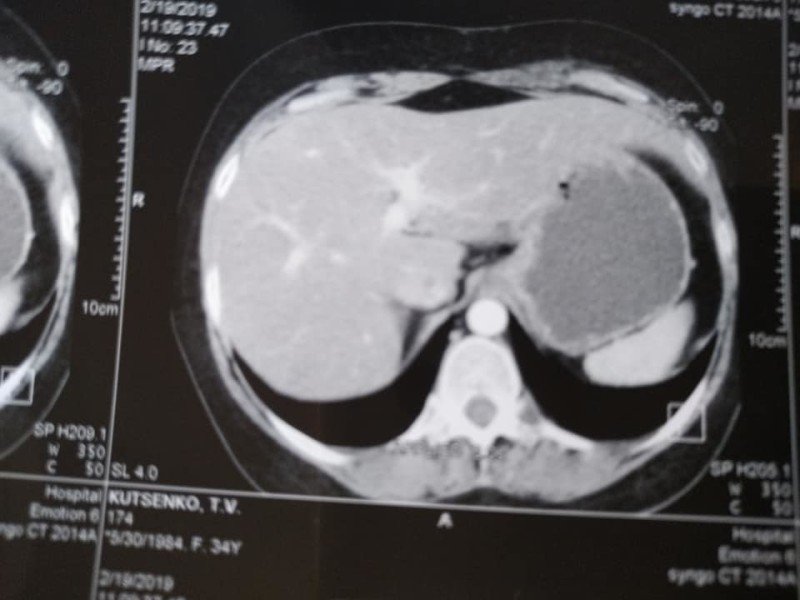

«У мене метастази, 4 стадія, але постійна від початку лікування позитивна динаміка. З 5 пухлин різних за розмірами в печінці, залишилася одна 12 на 10мм, яка була на початку 50мм. На першому фото печінки видно плями темні-це вони,метастази,а на другому фото теперішній стан. Це дуже успішне лікування. Ще трішки і я надіюсь і ця пухлина теж зникне», – розповіла вона.